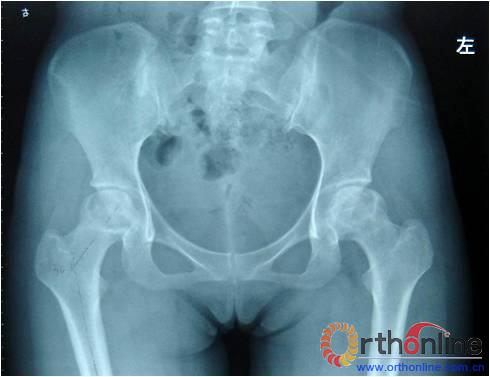

图为:方某,女,21岁,双侧激素性股骨头坏死,ARCO III-C期,C.F.P. 股骨假体THA前后双髋X线摄片。

图1、图2:术前;图3:术后;图4:术后3个月;图5:术后6个月;图6:术后1.2年